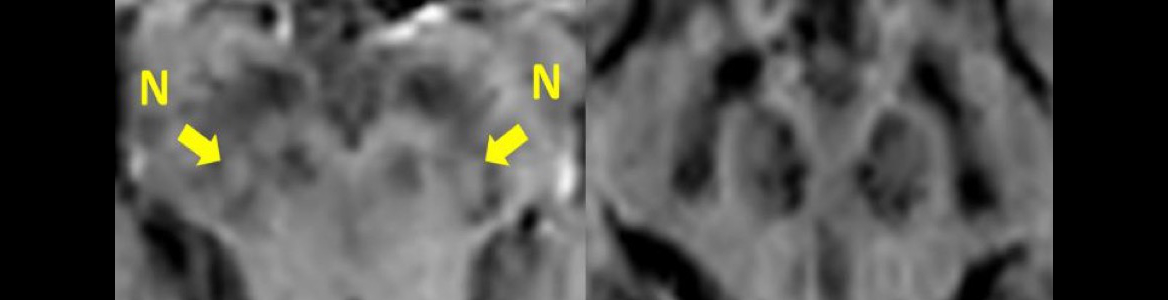

Bild: Bei Parkinson-Betroffenen führt das Absterben von Neuronen im Nigrosom 1 in der Substantia nigra dazu, dass die bei gesunden Menschen bestehende von signalarmen dunkleren Arealen umgebene signalreiche hellere längliche Struktur (N, entspricht dem sogenannten Nigrosom 1) in der eisengewichteten MRI Bildgebung (sogenannte Suszeptibilitätsgewichtete Bildgebung) fehlt.